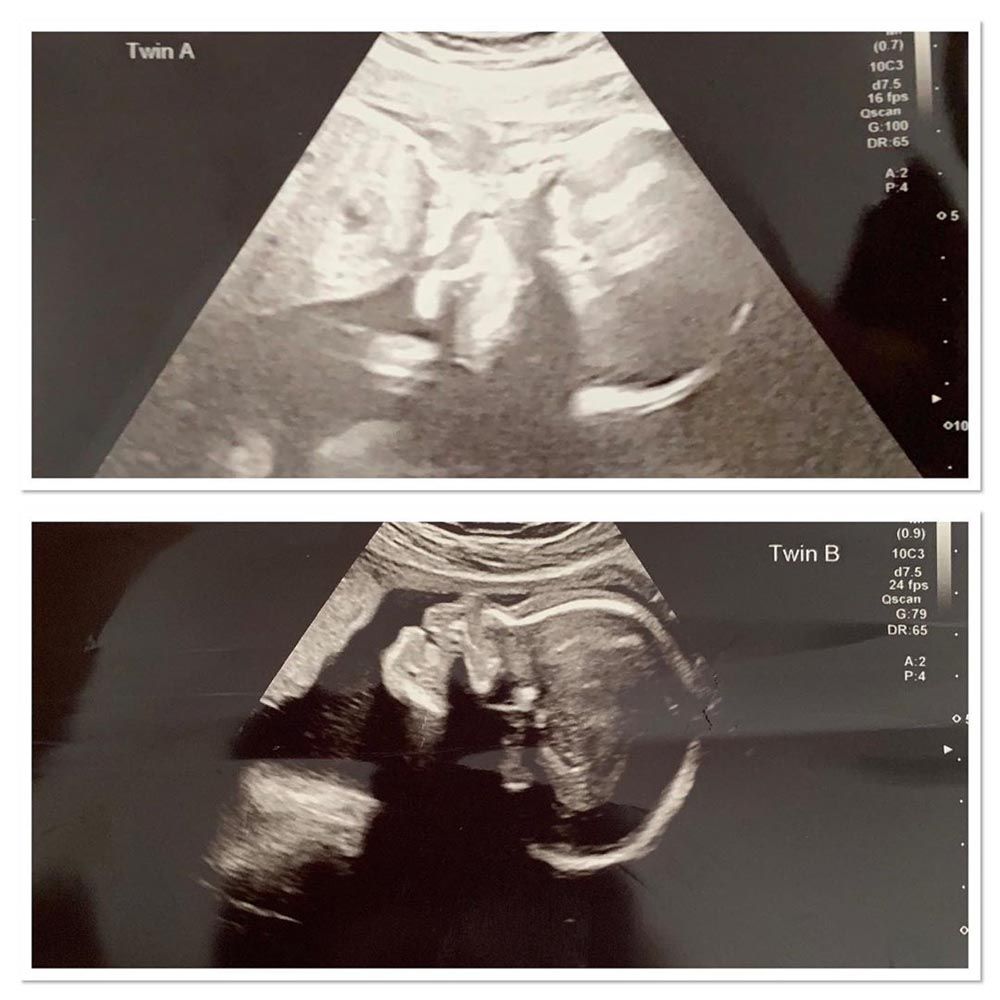

When Harriet Alderman, 21, discovered she was expecting Hugo and Hayze Zani, she was beside herself with excitement – only for a scan at 22 weeks to deliver a crushing blow.

Spotting a significant amniotic fluid imbalance between the boys, doctors diagnosed them with twin to twin transfusion syndrome (TTTS), which occurs when the blood flow between unborn babies is unequal.

Then, everything changed after her 22 week scan at Oxford's John Radcliffe Hospital near where her partner lives.

After spotting a fluid imbalance between the babies, doctors officially diagnosed TTTS.

Harriet continued: “Doctors told me the TTTS was stage three, which meant it was starting to affect Hayze's heart function. He was the recipient twin so was in a lot of fluid. Hugo, the donor twin, was not getting enough nutrients."